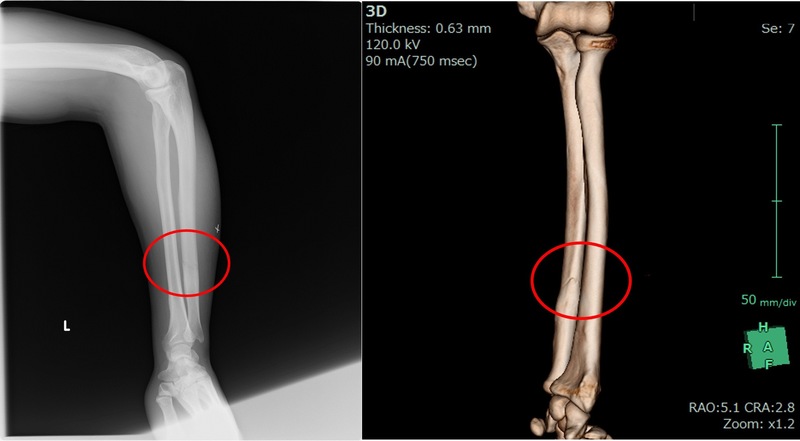

尺骨不全骨折

競技:野球

受傷原因:デッドボールによる直達外力

画像診断:尺骨骨幹部不全骨折

装着目的:試合出場にあたり患部脆弱性の補完・再発予防